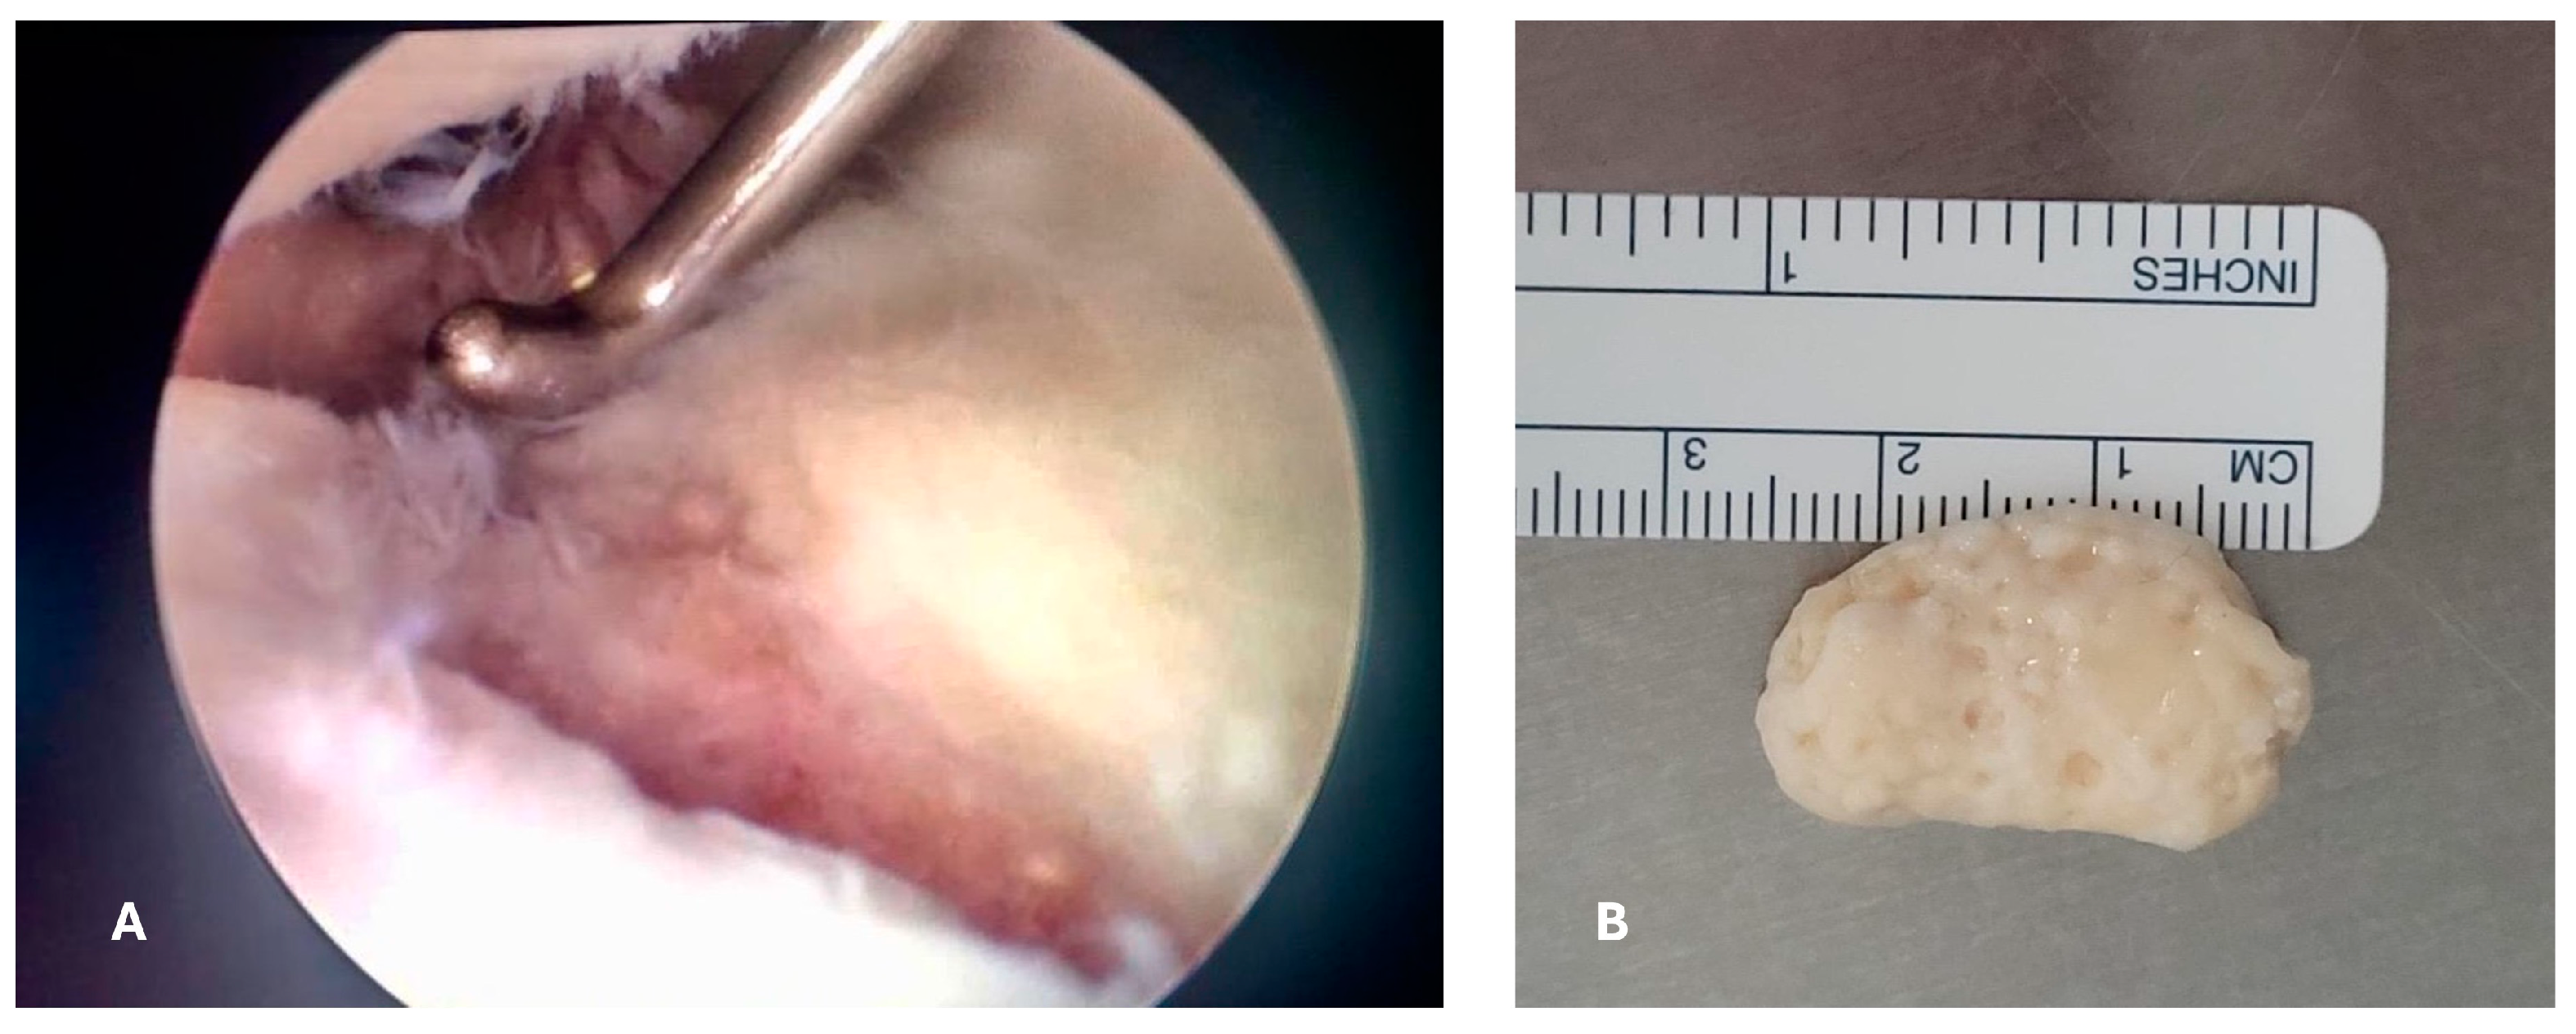

2. Case Report